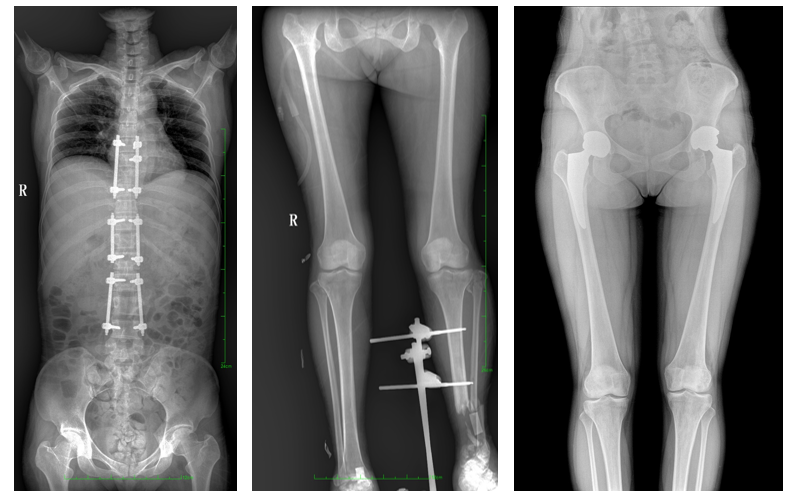

普愛醫(yī)療自主研發(fā),專為大視野臨床應用打造的平板動態(tài)DR——PLX8600,圖像不拼接,有效簡化影像科室檢查流程,提高診斷精度,降低患者吸收的輻射劑量。與市面常規(guī)多張攝影再軟件拼接DR相比,PLX8600解決了拼接圖像存在密度不均勻,拼接處圖像配準和放大效應等問題,輻射劑量是常規(guī)長骨軟件拼接DR的1/2或1/3,給患者更多關愛。

一、成像面積大。17"*34"有效視野,一次成像不拼接。相較于多張攝影再軟件拼接的DR設備,PLX8600解決了拼接圖像存在密度不均勻,拼接處圖像配準和放大效應等問題,給臨床帶來了大視野影像解決方案,可一次性覆蓋全脊柱或雙下肢影像。

PLX8600大視野平板動態(tài)DR攝影速度快,患者可以更快地完成檢查,且單次攝影輻射劑量是常規(guī)多張攝影再軟件拼接DR的1/2或1/3,低劑量給患者更多關愛。

PLX8600大視野平板動態(tài)DR可在低輻射劑量下獲得患者站立位、臥位的高質(zhì)量影像。搭載自主研發(fā)的圖像均衡處理系統(tǒng),能夠很好的均衡人體不同厚度組織的影像,視野大,圖像清晰,層次豐富。如果您想采購這款產(chǎn)品,歡迎聯(lián)系我們,咨詢電話400-025-6366。